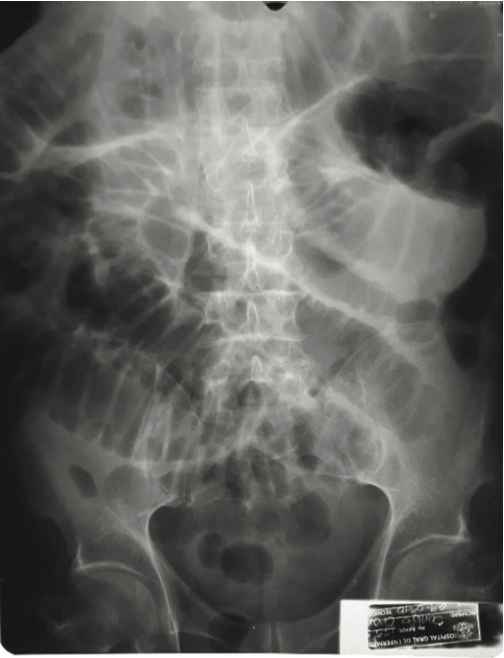

Durante la evaluación diagnóstica se presenta un cuadro de obstrucción intestinal con resolución espontanea, de- bido a que puede haber migración del lito intraluminal re- solviendo momentáneamente el cuadro obstructivo. En estudios de imágenes podemos mencionar inicialmente

hallazgos en rayos x que presenta neumobilia, dilatación de asas intestinales e imagen de un lito intraluminal (tria- da de Simon). En tomografía estos hallazgos son visualiza- dos con mayor calidad de imagen2,4.